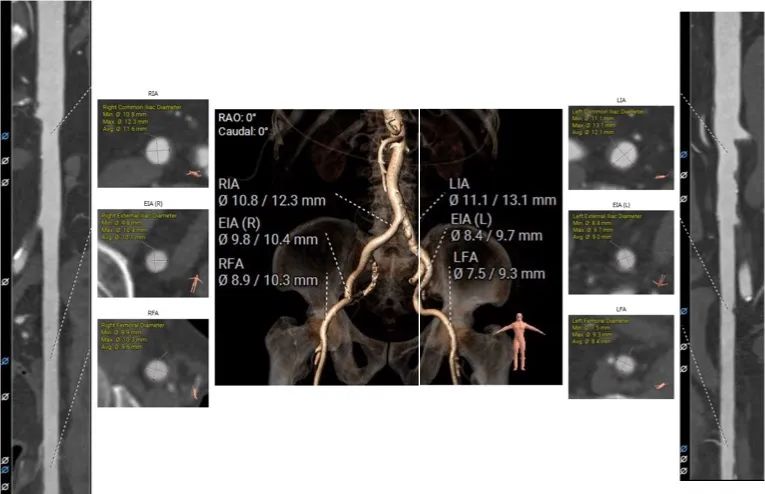

股动脉入路: